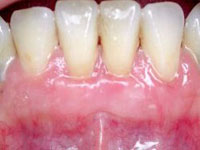

Treatment Options

The treatment approach depends on how advanced the condition is. Early stages can often be managed with non-surgical methods, while more advanced cases may require additional procedures.

• Professional cleaning: Removal of plaque and tartar

• Scaling and root planing: Deep cleaning below the gum line

• Medication: To control infection when required

• Maintenance care: Regular follow-up and monitoring